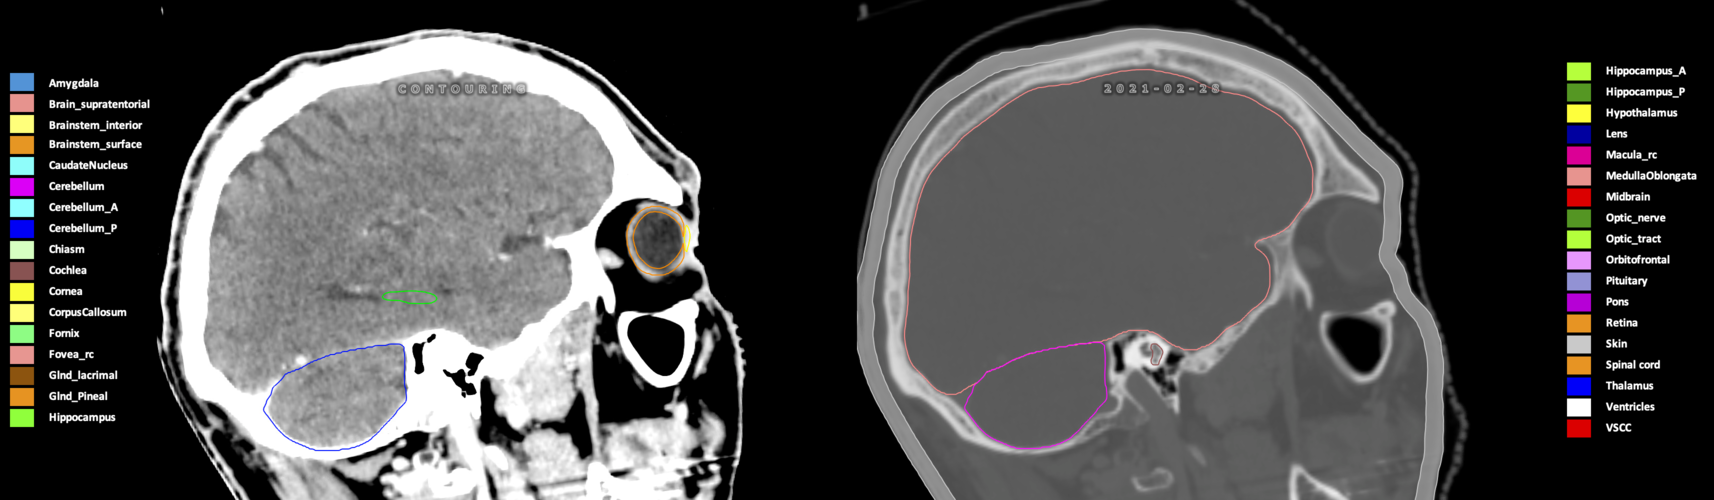

Included are all OARs known to be relevant for radiation-induced toxicity in neuro-oncology: brain, brainstem (midbrain, pons, medulla oblongata), chiasm, cerebellum (anterior & posterior), cochlea, cornea, hippocampus (anterior & posterior), hypothalamus, lens, lacrimal gland, optic nerve, pituitary, skin, and vestibular & semicircular canals. To further facilitate research on cognition, vision and radiological changes after irradiation of the brain, potential clinically-relevant OARs are included: amygdala, caudate nucleus, cerebellum (anterior & posterior), corpus callosum, fornix, macula, optic tract, orbitofrontal cortex, periventricular space (PVS), pineal gland, and thalamus.

Three-dimensional delineation of the 25 consensus OARs for neuro-oncology are shown on CT (WW/WL 120/40, 3000/600), 3T MR images, (T1Gd, T2FLAIR 1mm) and 7T MR (MP2RAGE 0.7 mm). All are presented in transversal, sagittal and coronal view.